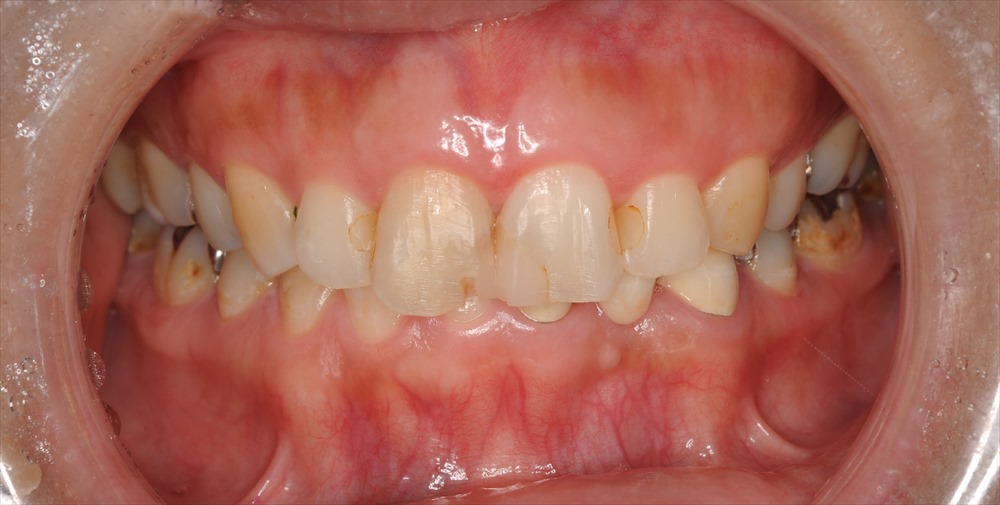

確かに前歯は今まで詰めてきた詰め物が割れ、変色をし神経がない事もあり右上の前歯は色が変わっています。歯茎が見えるガミースマイルだった為、歯肉形成外科をマイクロサージェリーで行い

歯の長さを獲得しました。

術前